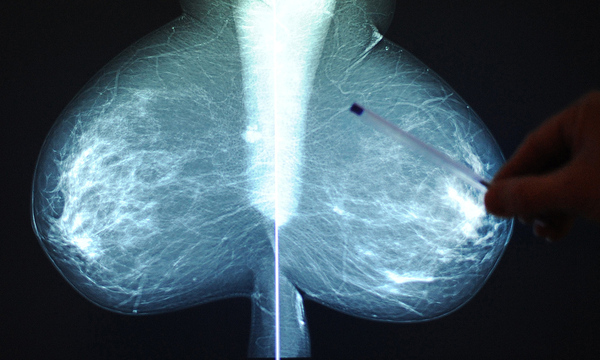

Facebooks Vorgehen gegen Darstellung nackter Haut, nimmt groteske Züge an. Das Unternehmen entschuldigt sich jetzt für das gelöschte Präventionsvideo mit animierten Frauen.

Die Schwedische Krebsgesellschaft Cancerfonden hatte am Donnerstag in einem offenen Brief an Facebook kritisiert, dass die Bilder wegen ihrer "Anzüglichkeit" entfernt worden seien. In dem Video, das zum präventiven Abtasten der Brust nach verdächtigen Knoten anleitet, seien animierte Frauen mit kreisrunden Brüsten zu sehen.

Cancerfonden habe die Löschung anfechten wollen, habe aber niemanden bei Facebook erreichen können. "Wir finden es unverständlich und seltsam, wie jemand medizinische Informationen anzüglich finden kann", sagte Cancerfonden-Sprecherin Lena Biornstad.